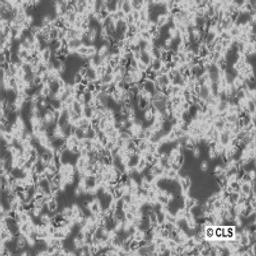

Chinese Hamster Ovary cell line CHO

Morphology: Epithelial

Growth Properties: Monolayer, adherent

Description: The CHO (Chinese hamster ovary) cell line was established in the 1960s from the ovary of the Chinese hamster. CHO cells are used in studies of genetics, toxicity screening, nutrition and gene expression, particularly to express recombinant proteins. Application: as mammalian host for the production of recombinant protein therapeutics.